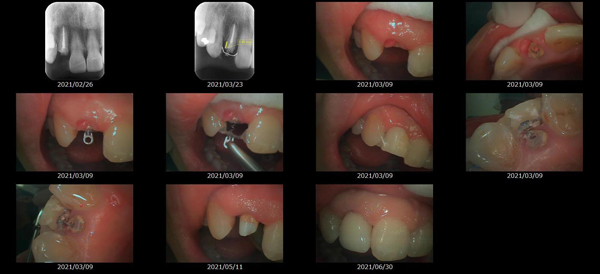

救歯MTM

虫歯が大きくて残せない歯、転倒などの事故により歯が根の深いとこで折れてしまったなどで、抜かざるを得ない歯を、骨の中に埋まっている健全な根を、骨の上に矯正的に引き上げることで、その歯を抜かず温存、救歯できる可能性のある治療方法です。

この特別な診療である救歯MTMは、以下のような特徴があります。

①健全な歯を、歯肉から見える位置にまで引き上げることで

根の治療の成功率を上げることが出来る。唾液には沢山の細菌がいます。唾液が入らない環境での根の治療を(神経の治療)を行うことで神経の治療、根の治療の成功率は格段と上がります。

②骨の上にある歯と土台で支える被せもの製作できる。

被せものを土台だけに頼ることなく、引き上げた健全な歯でも支えることで、歯への被せ物がしっかりと装着できるようになる。

③抜かずに歯を活かすことで、隣の歯を削るブリッジやインプラントにしないで済むことがある。

歯を矯正的に引き上げることで、その歯を救歯できるだけでなく、隣の歯を削るなどの侵襲を回避できる場合がある。

救歯治療と審美性の両立

当院では様々な治療の基礎に審美と機能の両立というテーマがあります。

リスク

- > 歯を矯正的に引き上げることで、骨の中の根の長さは短くなりますが、その短さでも安定するという診断をした場合のみ施術になります。 残せる歯、根の長さが短い場合は、この救歯MTMの治療対象とならない場合がございます。

- > 治療期間が数か月~1年に及ぶ場合がある。

- > 費用が自費診療 44,000円 ~ 66,000円

- > 救歯MTMは救歯BTAセラミックと併用治療が必要な場合があります。

症例